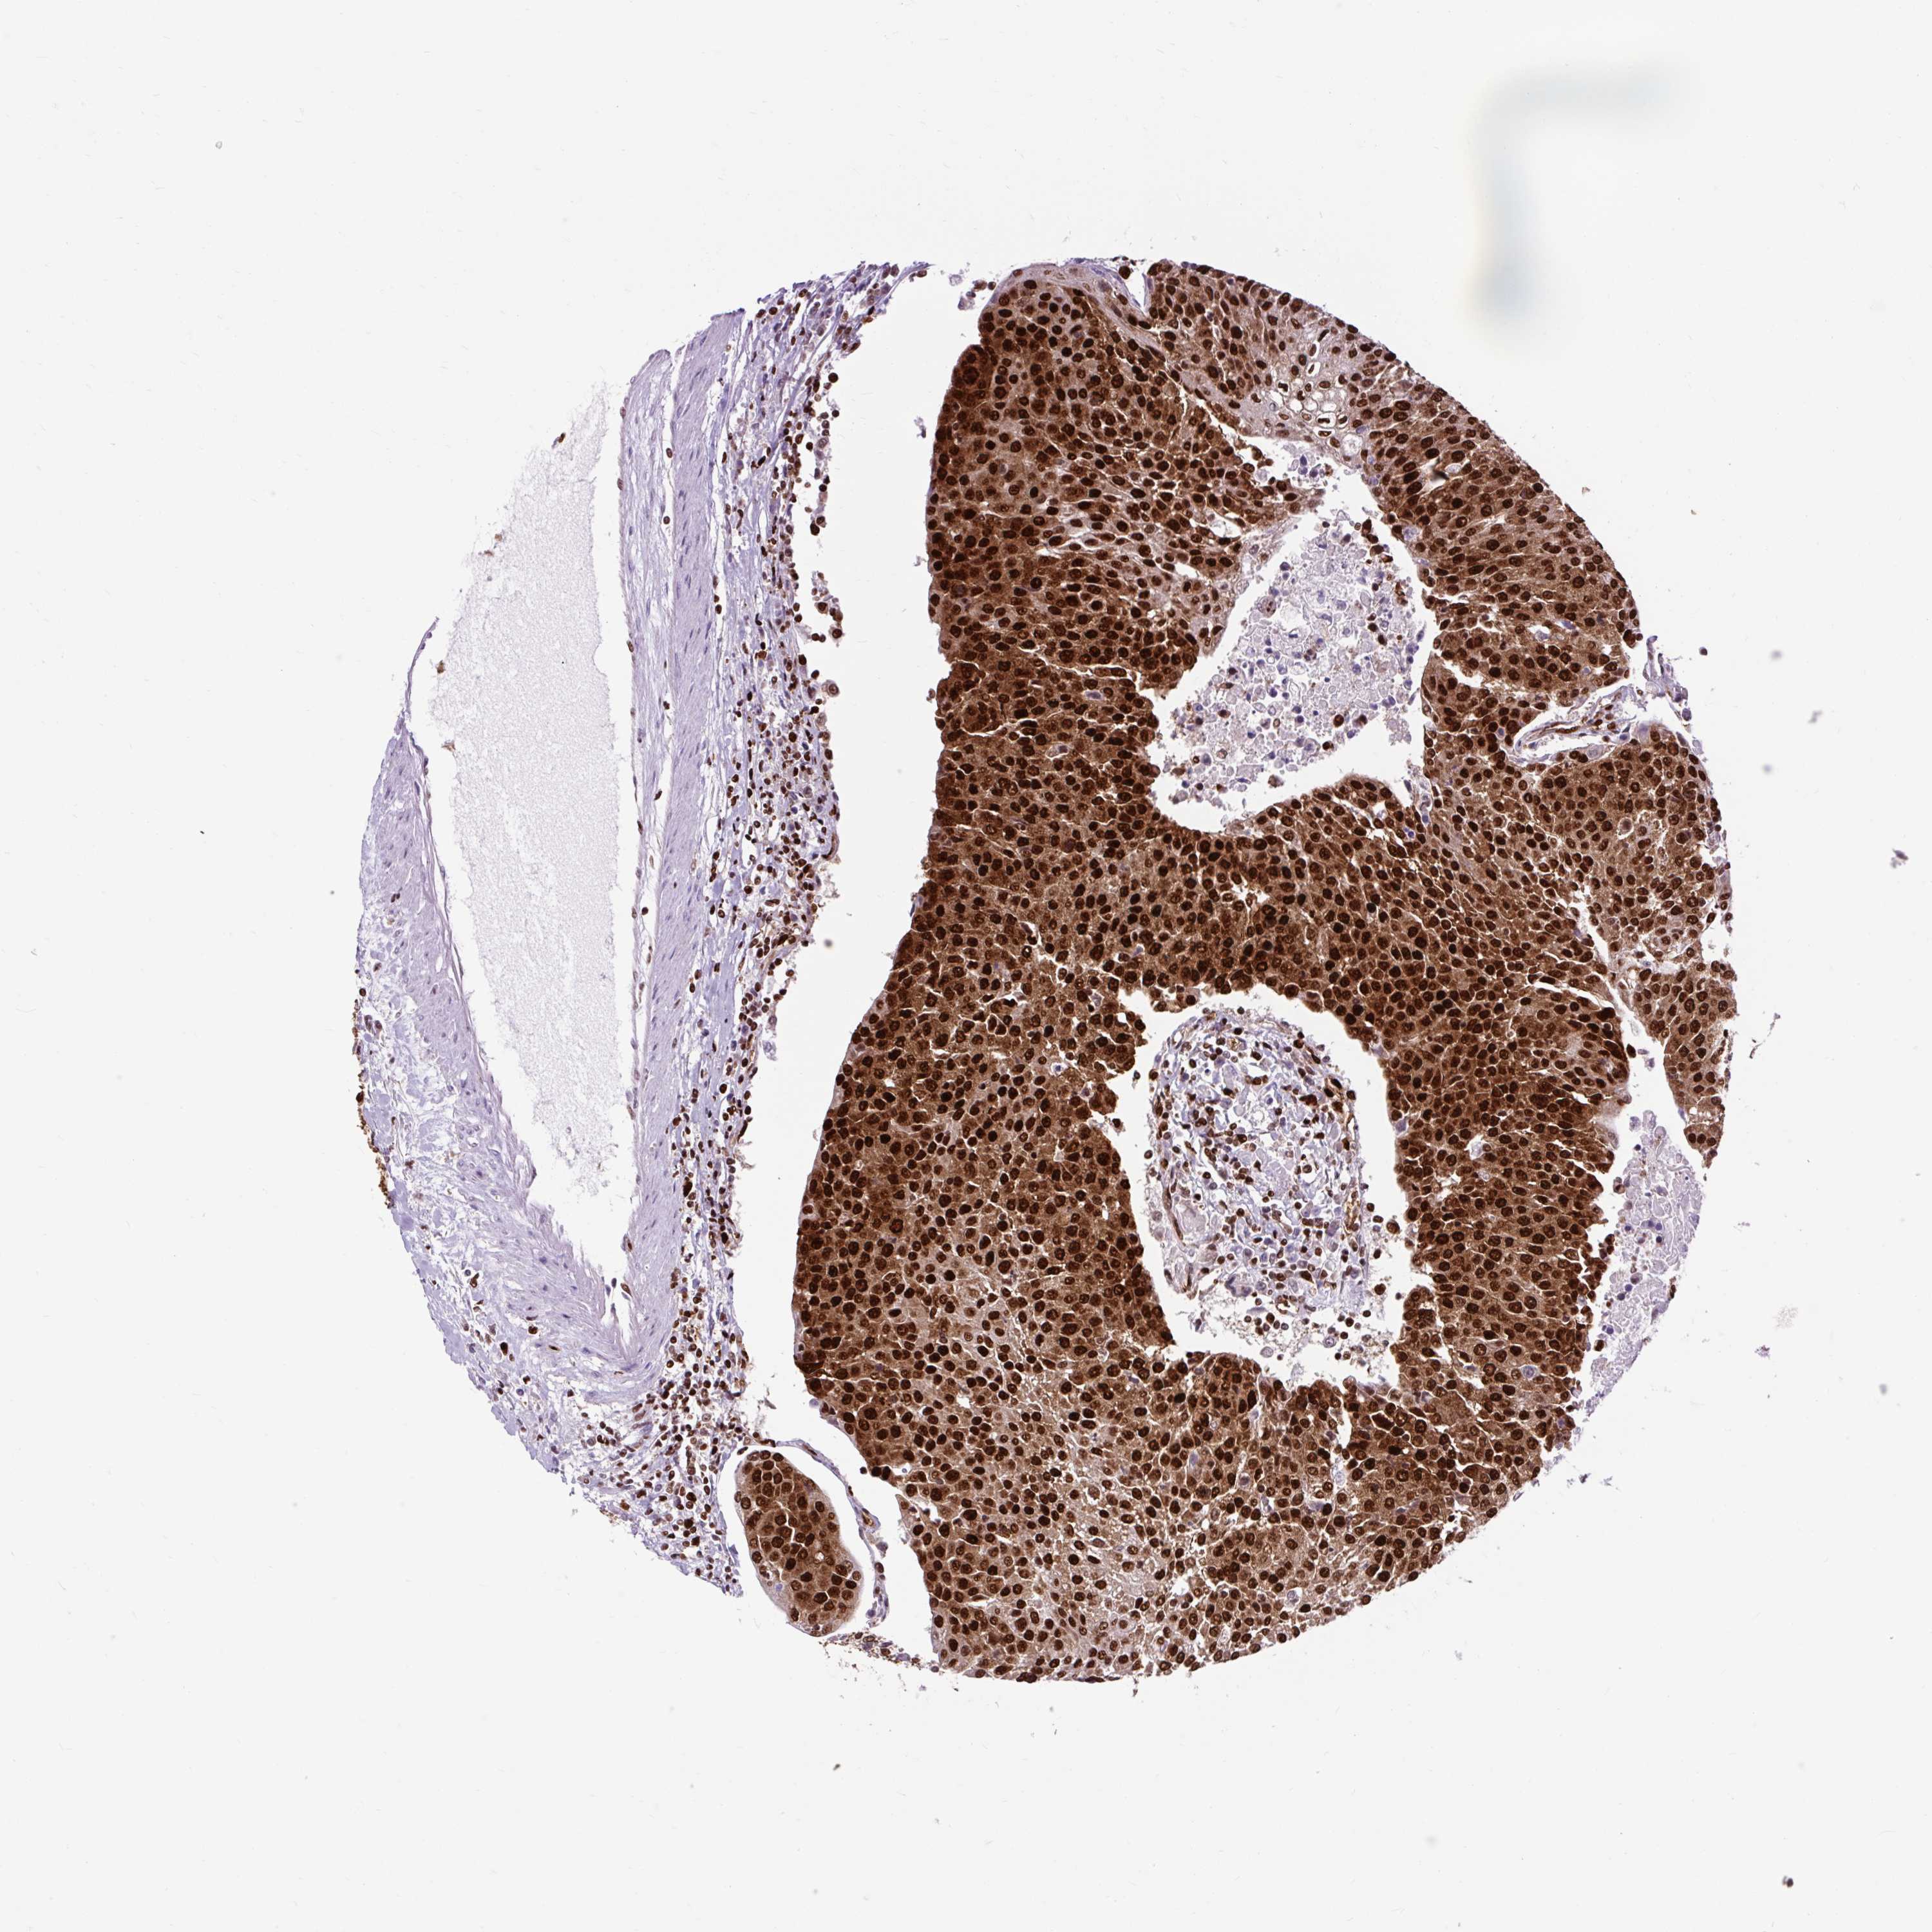

UROTHELIAL CANCER - Protein expressioni

A mouse-over function shows sample information and annotation data. Click on an image to view it in a full screen mode. Samples can be filtered based on level of antibody staining by selecting one or several of the following categories: high, medium, low and not detected. The assay and annotation is described here.

Note that samples used for immunohistochemistry by the Human Protein Atlas do not correspond to samples in the TCGA dataset.

Antibody stainingi

Antibody staining in the annotated cell types in the current human tissue is reported as not detected, low, medium, or high, based on conventional immunohistochemistry profiling in selected tissues. This score is based on the combination of the staining intensity and fraction of stained cells.

Each image is clickable and will lead to virtual microscopy that enables deeper exploration of all samples and also displays staining intensity scores, fraction scores and subcellular localization as well as patient and tissue information for each sample.

Antibody HPA008784

Antibody CAB033036

Antibody CAB058691

Staining

High

Medium

Low

Not detected

Intensity

Strong

Moderate

Weak

Negative

Quantity

>75%

75%-25%

<25%

None

Location

Nuclear

Cytoplasmic/membranous

Cytoplasmic/membranous,nuclear

Urothelial carcinoma, Low grade

Urothelial carcinoma, High grade

Urothelial carcinoma, NOS